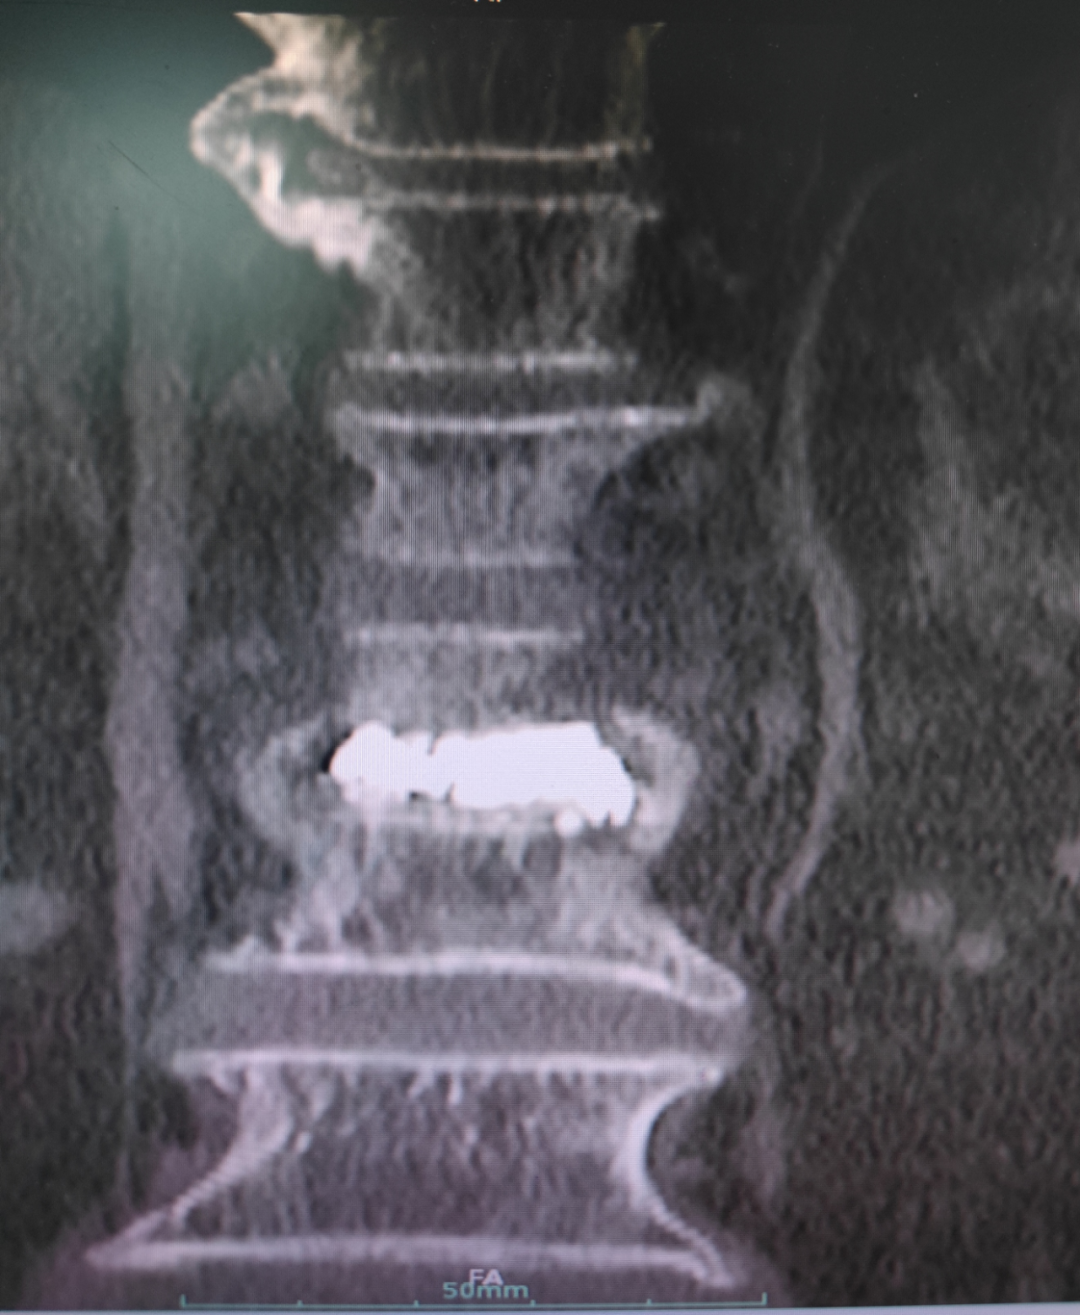

病例回顧 骨折部位 術(shù)中C臂協(xié)助定位 在C-臂監(jiān)視器透視下,分別定位胸12雙側(cè)椎弓根位置,標記穿刺點,僅以穿刺點為中心做3mm切開,在透視下注入骨水泥,再次透視見骨水泥位置良好。 骨水泥注入 術(shù)后影像學檢查 手術(shù)切口1cm左右 該手術(shù)經(jīng)皮透視下穿刺,手術(shù)切口小,創(chuàng)傷小,無需縫合,術(shù)后患者即感腰部疼痛明顯減輕,第二天可下床行走,已無腰痛不適,張大娘非常高興,自己再也不會受腰痛折磨整日與床為伴了。 我院脊柱骨科近年來,已成功開展多臺PVP手術(shù),為廣大老年患者減輕了病痛,減少了患者臥床時間,提高了生活質(zhì)量,是骨質(zhì)疏松性椎體骨折患者的福音。如果家里的老人突然出現(xiàn)了腰背疼痛,翻身下床困難,或者出現(xiàn)了腹部不適,排除腹部疾病(因為很多胸腰椎骨折患者在早期以腹痛腹脹為最主要癥狀),無論有沒有外傷史,建議帶老人及早就醫(yī),如果發(fā)現(xiàn)椎體損傷,積極治療,讓老人度過一個輕松愉快的晚年生活。 科普小講堂:經(jīng)皮椎體成形術(shù) 什么是骨質(zhì)疏松性椎體骨折? 骨質(zhì)疏松性椎體壓縮骨折,即在日常生活中患者并未遭受到明顯的外力而發(fā)生的骨折。這種骨折與創(chuàng)傷性的骨折不同,是由于自身骨質(zhì)疏松所導(dǎo)致的骨組織病變。骨質(zhì)疏松性骨折發(fā)生時,患者會感覺到背部明顯疼痛,翻身或起床等動作會讓疼痛更加明顯。 骨質(zhì)疏松性椎體壓縮骨折的危害有哪些? 一旦椎體發(fā)生骨質(zhì)疏松性椎體壓縮骨折,常常會導(dǎo)致患者出現(xiàn)腰背部持續(xù)性疼痛、季肋部放射痛、后凸畸形、呼吸功能受限及胃腸道癥狀等諸多癥狀,造成老年患者生活質(zhì)量下降。 什么是經(jīng)皮椎體成形術(shù)? (Percutaneousvertebroplasty,PVP)是一種新型的脊柱微創(chuàng)手術(shù),通過采用經(jīng)皮穿刺的方法,經(jīng)過椎弓根或是直接向椎體中注入骨水泥,使得椎體的強度和穩(wěn)定性得以提升,防止塌陷,從而達到緩解腰背疼痛,甚至部分恢復(fù)椎體高度的目的。 PVP手術(shù)優(yōu)點是什么? 1.恢復(fù)顯著:通常術(shù)后6個小時即能達到穩(wěn)定固定,患者可下床站立活動,大大縮短了患者臥床的時間。 2.疼痛減輕:術(shù)后患者會發(fā)現(xiàn)腰背部疼痛明顯減輕。 3.微創(chuàng):該治療方法僅需在皮膚上留2-3mm的穿刺針孔。 4.安全性:由于手術(shù)采用的是局部麻醉,因此即便是存在多種基礎(chǔ)病的患者也能夠耐受手術(shù),整個手術(shù)過程相對安全。 就診地址 酒泉市中醫(yī)醫(yī)院四樓脊柱骨科 咨詢電話 一樓門診部:0937-2669161 王醫(yī)生:13209409826 ??? 張醫(yī)生:18219971722